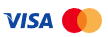

Пациент 55 лет.

Жалобы на невозможность полноценного пережевывания пищи, дефект дикции, отсутствие эстетики.

Диагноз: частичная вторичная адентия, генерализированный пародонтит на в.ч и н.ч

Жалобы на невозможность полноценного пережевывания пищи, дефект дикции, отсутствие эстетики.

Диагноз: частичная вторичная адентия, генерализированный пародонтит на в.ч и н.ч